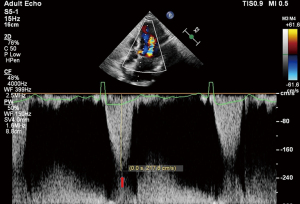

Following implantation, TEE revealed significant improvement with only mild residual MR. The residual mitral valve orifice area was 1.6 cm2, and the mean diastolic trans-mitral pressure gradient increased to 4 mmHg. The LVOT gradient decreased to 81 mmHg. Invasive hemodynamic monitoring showed left atrial pressure dropped significantly from 55 mmHg pre-procedure to 25 mmHg post-procedure. Pulmonary vein flow spectrum normalized (Figure 5).